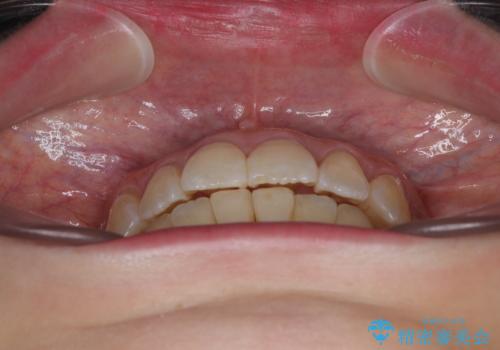

前歯のデコボコをインビザラインで目立たずに改善

- 上下前歯のデコボコを気にして来院された患者様です。

デコボコは顕著であるものの、口元の突出感は強くないため、非抜歯にて矯正治療を行うこととしました。

装置はワイヤー装置でもマウスピースでも対応可能でしたが、より目立たない装置をご希望とのことで、インビザラインにて矯正治療を行うこととしました。